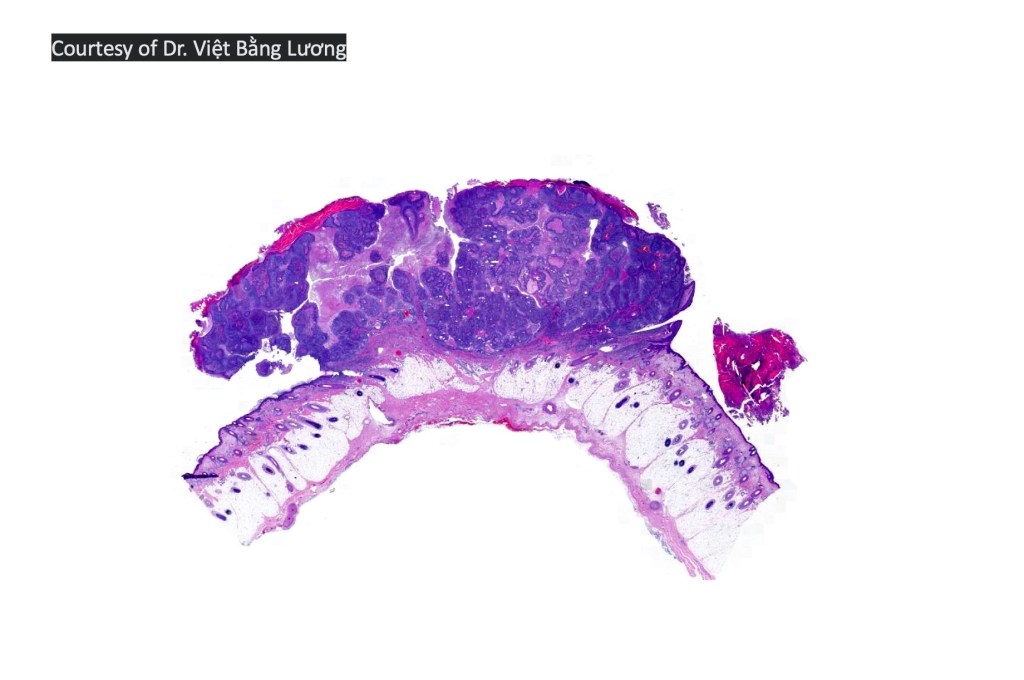

•Well differentiated lobular growth pattern though to a poorly differentiated tumor often showing a diffuse, infiltrating border which may extend into the subcutaneous fat

•Comedo type necrosis commonly present

•Tumors are composed of an admixture of darkly staining basaloid cells with hyperchromatic or vesicular nuclei and more obvious sebaceous cells with eosinophilic, bubbly, multivacuolated cytoplasm frequently indenting the nucleus (scalloped)